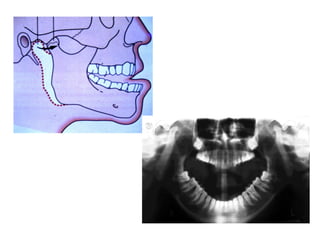

Oro-antral communication

Large antrum

Lone-standing tooth in an atrophic maxilla

Large splayed roots

Fracture of tuberosity

History of antral involvement

Plastic Closure of Oroantral Fistula